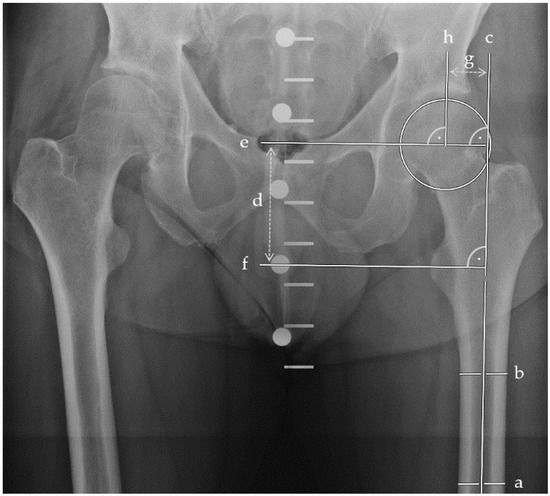

Only a few patients had complications when treating their femoral neck fracture with a DHS with an anti-rotational screw. For example, a 57-year-old female patient was transferred to our hospital following a fall from standing height. She had a Pauwels type 3, Garden type 4 fracture (Figure 5a) and was treated with a DHS with an anti-rotational screw (Figure 5b). Despite an initially satisfactory follow-up, she presented with an avascular necrosis of the femoral head six months following surgery (Figure 5c), which required conversion to total hip arthroplasty. However, most patients treated with a DHS with an anti-rotational screw had a satisfactory outcome. For instance, a 40-year-old male patient also presented with a Pauwels type 3, Garden type 4 fracture (Figure 5d) and received a DHS with an anti-rotational screw (Figure 5e). The follow-up result was inconspicuous, and the fracture healed (Figure 5f).

Figure 5.

Outcomes of femoral neck fractures when treated with a DHS with anti-rotational screw: (a) A 57-year-old female patient presented with a highly unstable femoral neck fracture, (b) which was treated with a DHS with an anti-rotational screw, but (c) developed an avascular necrosis of her hip. In comparison, (d) a 40-year-old male patient presented with a comparable fracture morphology, (e) underwent analogous treatment, and (f) demonstrated favorable postoperative results.